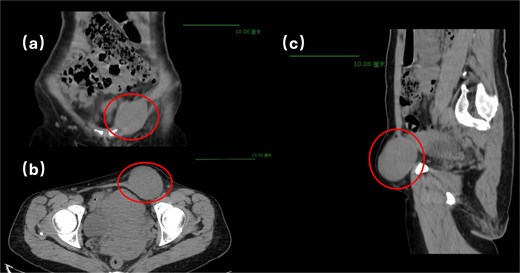

Physical examination revealed a soft, non-tender abdomen without hepatosplenomegaly or shifting dullness; normal bowel sounds were auscultated. A 5 × 5 cm firm, well-circumscribed mass with smooth surface contour and mild tenderness was palpated in the left inguinal region, demonstrating irreducibility and resistance to manual compression. Preoperative imaging modalities—contrast-enhanced computed tomography (Fig. 1) and grayscale ultrasonography (Fig. 2)—suggested a provisional diagnosis of uterine fibroid.

Surgical intervention comprised en bloc excision of the mass with the affected round ligament segment, followed by laparoscopic tension-free mesh hernioplasty (Fig. 3). Histopathological analysis confirmed uterine adenomyoma (Fig. 4). The patient was discharged on postoperative Day 5 following an uneventful recovery.